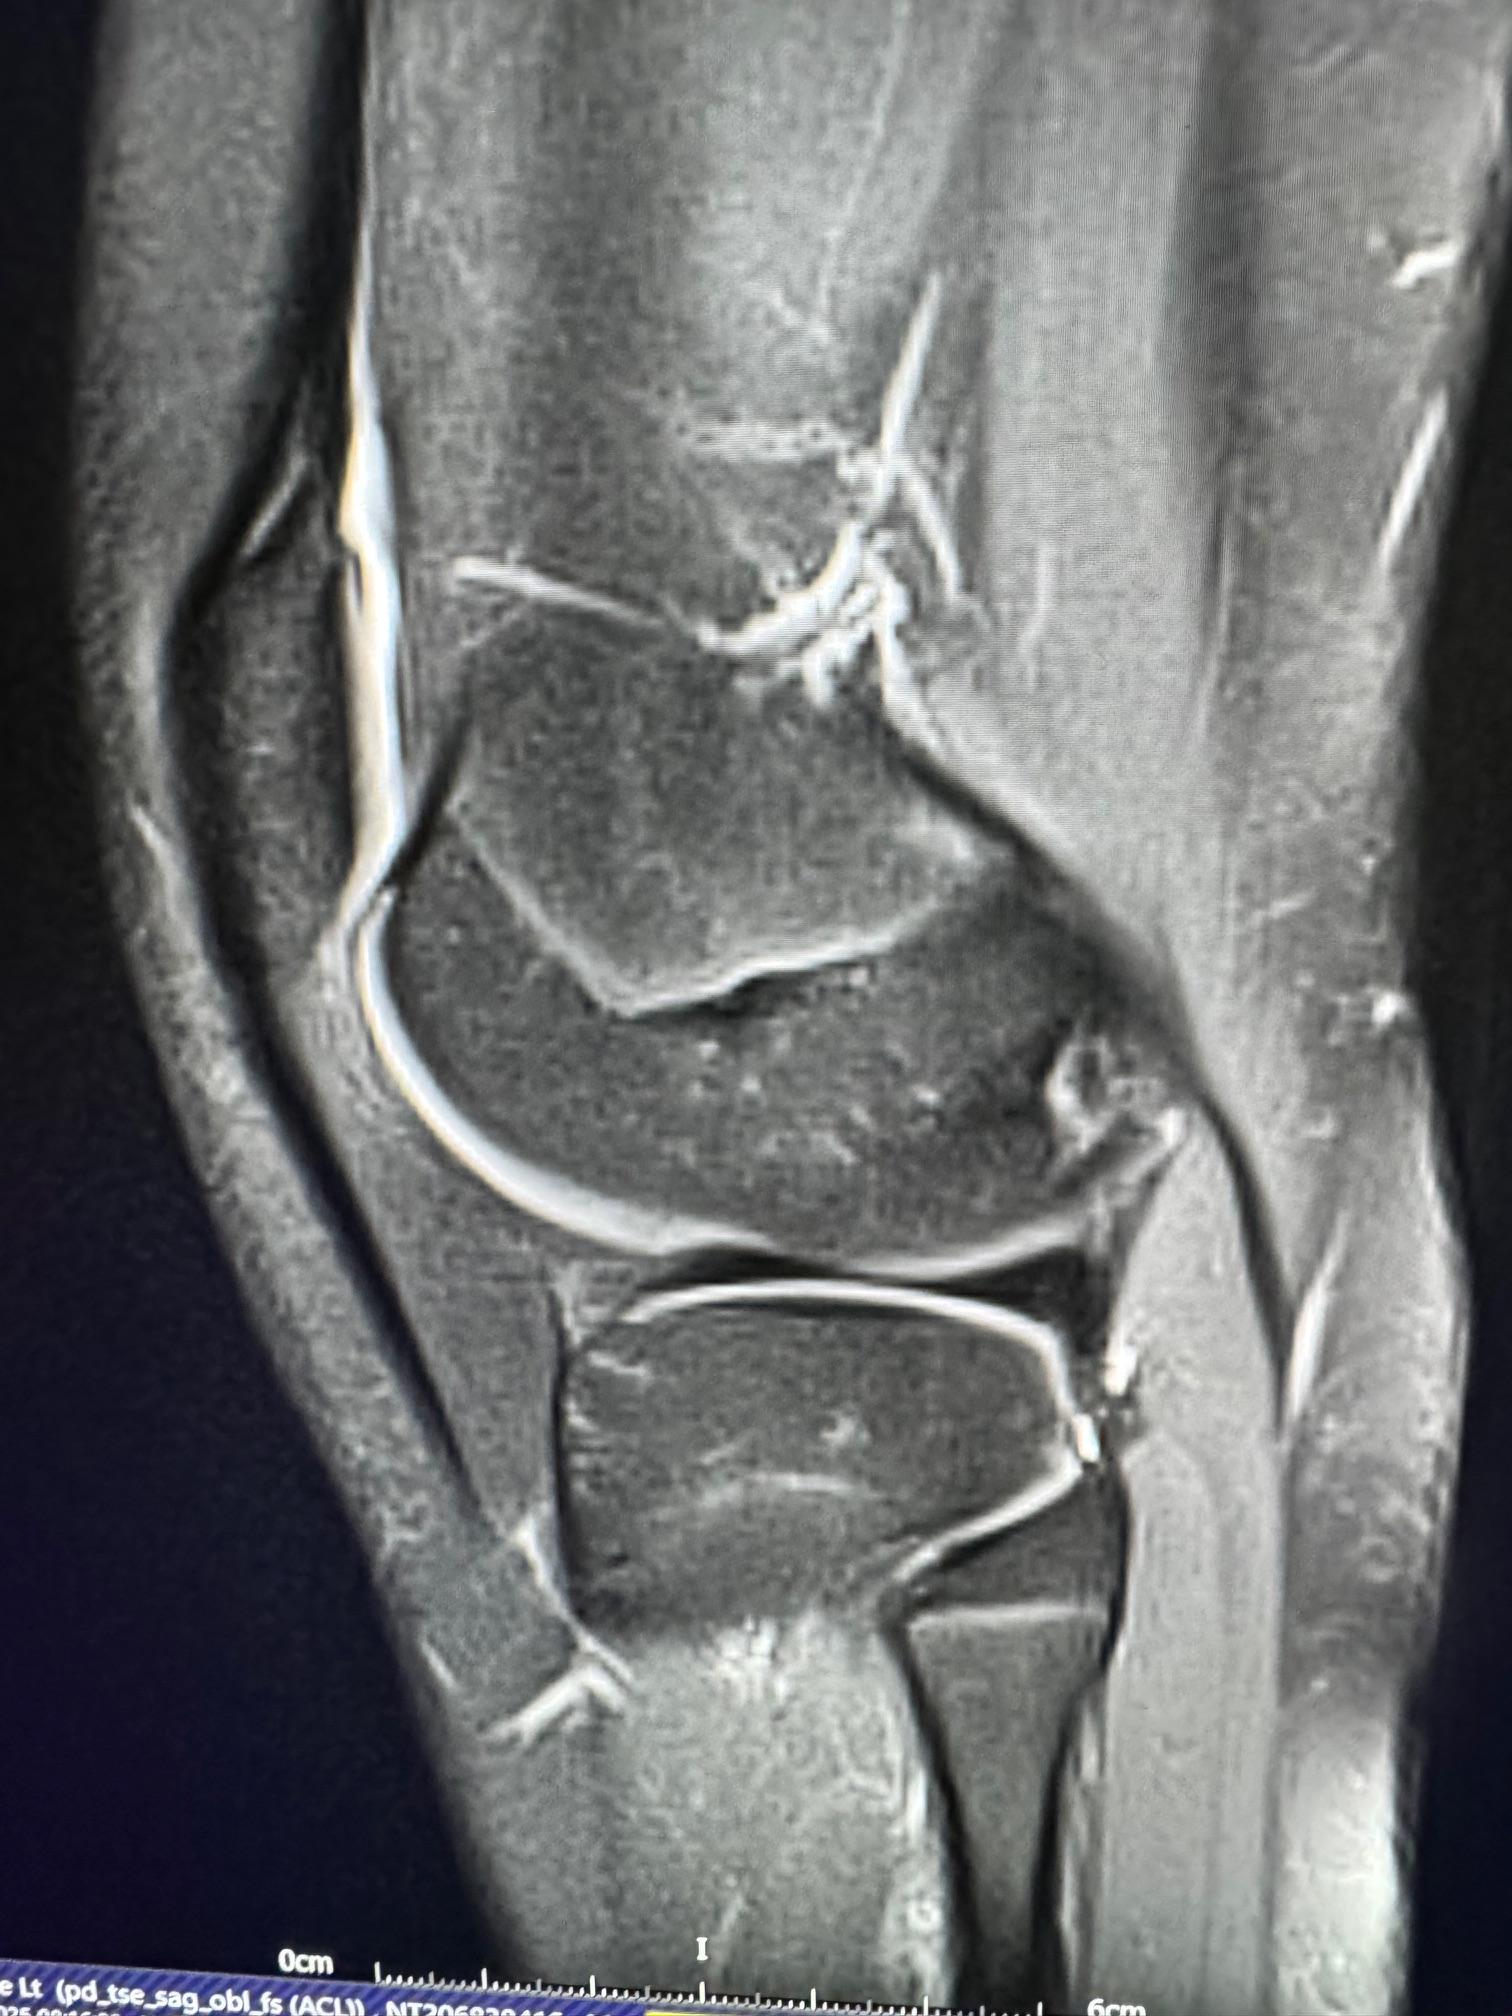

image7